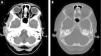

Se presenta una niña de 9 años con fiebre elevada, otalgia derecha, otorrea y cefalea temporal ipsilateral. En la exploración destacaba tumefacción dolorosa sobre arco cigomático derecho, trismo y eritema retroauricular. La TAC mostró mastoiditis derecha con absceso subperióstico temporal y mínimo trombo no oclusivo en seno sigmoide (fig. 1). En la analítica destacaba elevación de reactantes de fase aguda. Se inició antibioterapia con cefotaxima y clindamicina, con buena evolución posterior. En cultivo se aisló flora saprófita.

Imagen de TAC. A. Ventana de partes blandas, con contraste endovenoso: mastoiditis derecha con absceso subperióstico temporal de 3,5mm y mínimo trombo no oclusivo en seno sigmoide. Se aprecia aumento asimétrico de partes blandas indicativo de miositis reactiva del músculo temporal. B. Imagen axial en ventana de hueso en la que se percibe retención de secreciones otomastoideas.